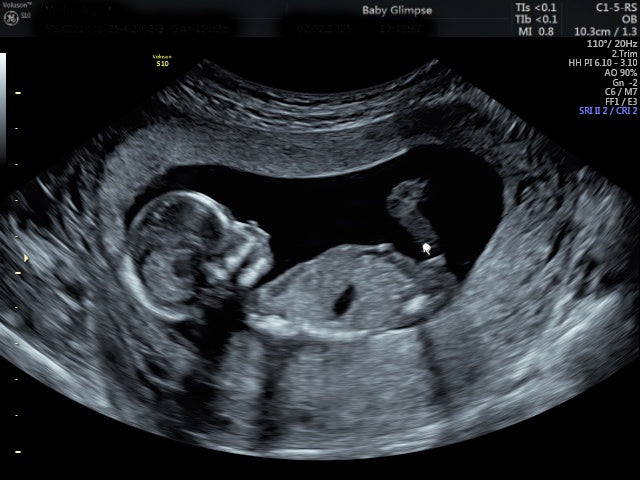

Een kinderwens is een van de meest bijzondere beslissingen in het leven. Toch realiseren veel vrouwen (en stellen) zich niet dat een zwangerschap al maanden vóór de bevruchting begint. Het lichaam bereidt zich namelijk in stilte voor: eicellen rijpen, hormonen veranderen en het lichaam legt de bouwstenen klaar die nodig zijn om een nieuw leven te laten ontstaan.

Wetenschappelijk onderzoek toont aan dat de eerste 1000 dagen, vanaf de conceptie tot het tweede levensjaar, cruciaal zijn voor de gezondheid van een kind op de lange termijn. Juist daarom is het belangrijk dat vrouwen (en hun partners) al tijdens de kinderwens bewust met voeding, leefstijl en supplementen omgaan.

De eerste 12 weken van de zwangerschap

Zodra de bevruchting heeft plaatsgevonden, breken 12 belangrijke en bepalende weken aan. In deze fase worden alle organen en de placenta aangelegd. Dit wordt niet voor niets de cruciale fase van de zwangerschap genoemd.

In deze periode heeft het lichaam een verhoogde behoefte aan energie en voedingsstoffen. Het embryo verdubbelt vaak in grootte per week, wat aangeeft hoeveel celdelingen er per dag plaatsvinden. Al deze celdelingen horen foutloos te verlopen, voor het behoud van een gezonde zwangerschap en het ontwikkelen van een gezond kind. Dit vraagt om goede ondersteuning met de juiste vitaminen en mineralen.